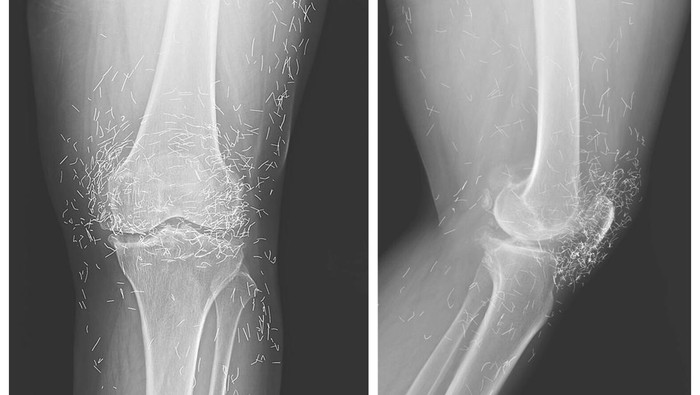

Dokter di Korea Selatan menemukan ratusan 'susuk' emas di lutut seorang pasien nenek 65 tahun. Dalam sebuah foto rontgen yang beredar, tampak ada ratusan benang emas yang tertanam di lutut pasien tersebut. Apa yang sebenarnya terjadi?

Pasien yang tidak disebutkan namanya itu memutuskan untuk kembali lagi ke rumah sakit. Hasil rontgen menunjukkan tulang kering di bagian dalam sendi telah menebal dan mengeras. Dokter menemukan adanya pertumbuhan tulang pada bagian dalam tulang kering dan tulang paha di sekitar sendi lutut.

Dokter yang memeriksa pasien juga menemukan ratusan bintik kecil pada rontgen di sekitar sendi lutut, yang ternyata adalah benang-benang emas berukuran kecil.

Benang-benang emas itu dimasukkan sebagai bagian dari terapi akupuntur yang dijalani pasien. Benang itu sengaja ditinggalkan dalam jaringan untuk memberikan rangsangan terus-menerus.